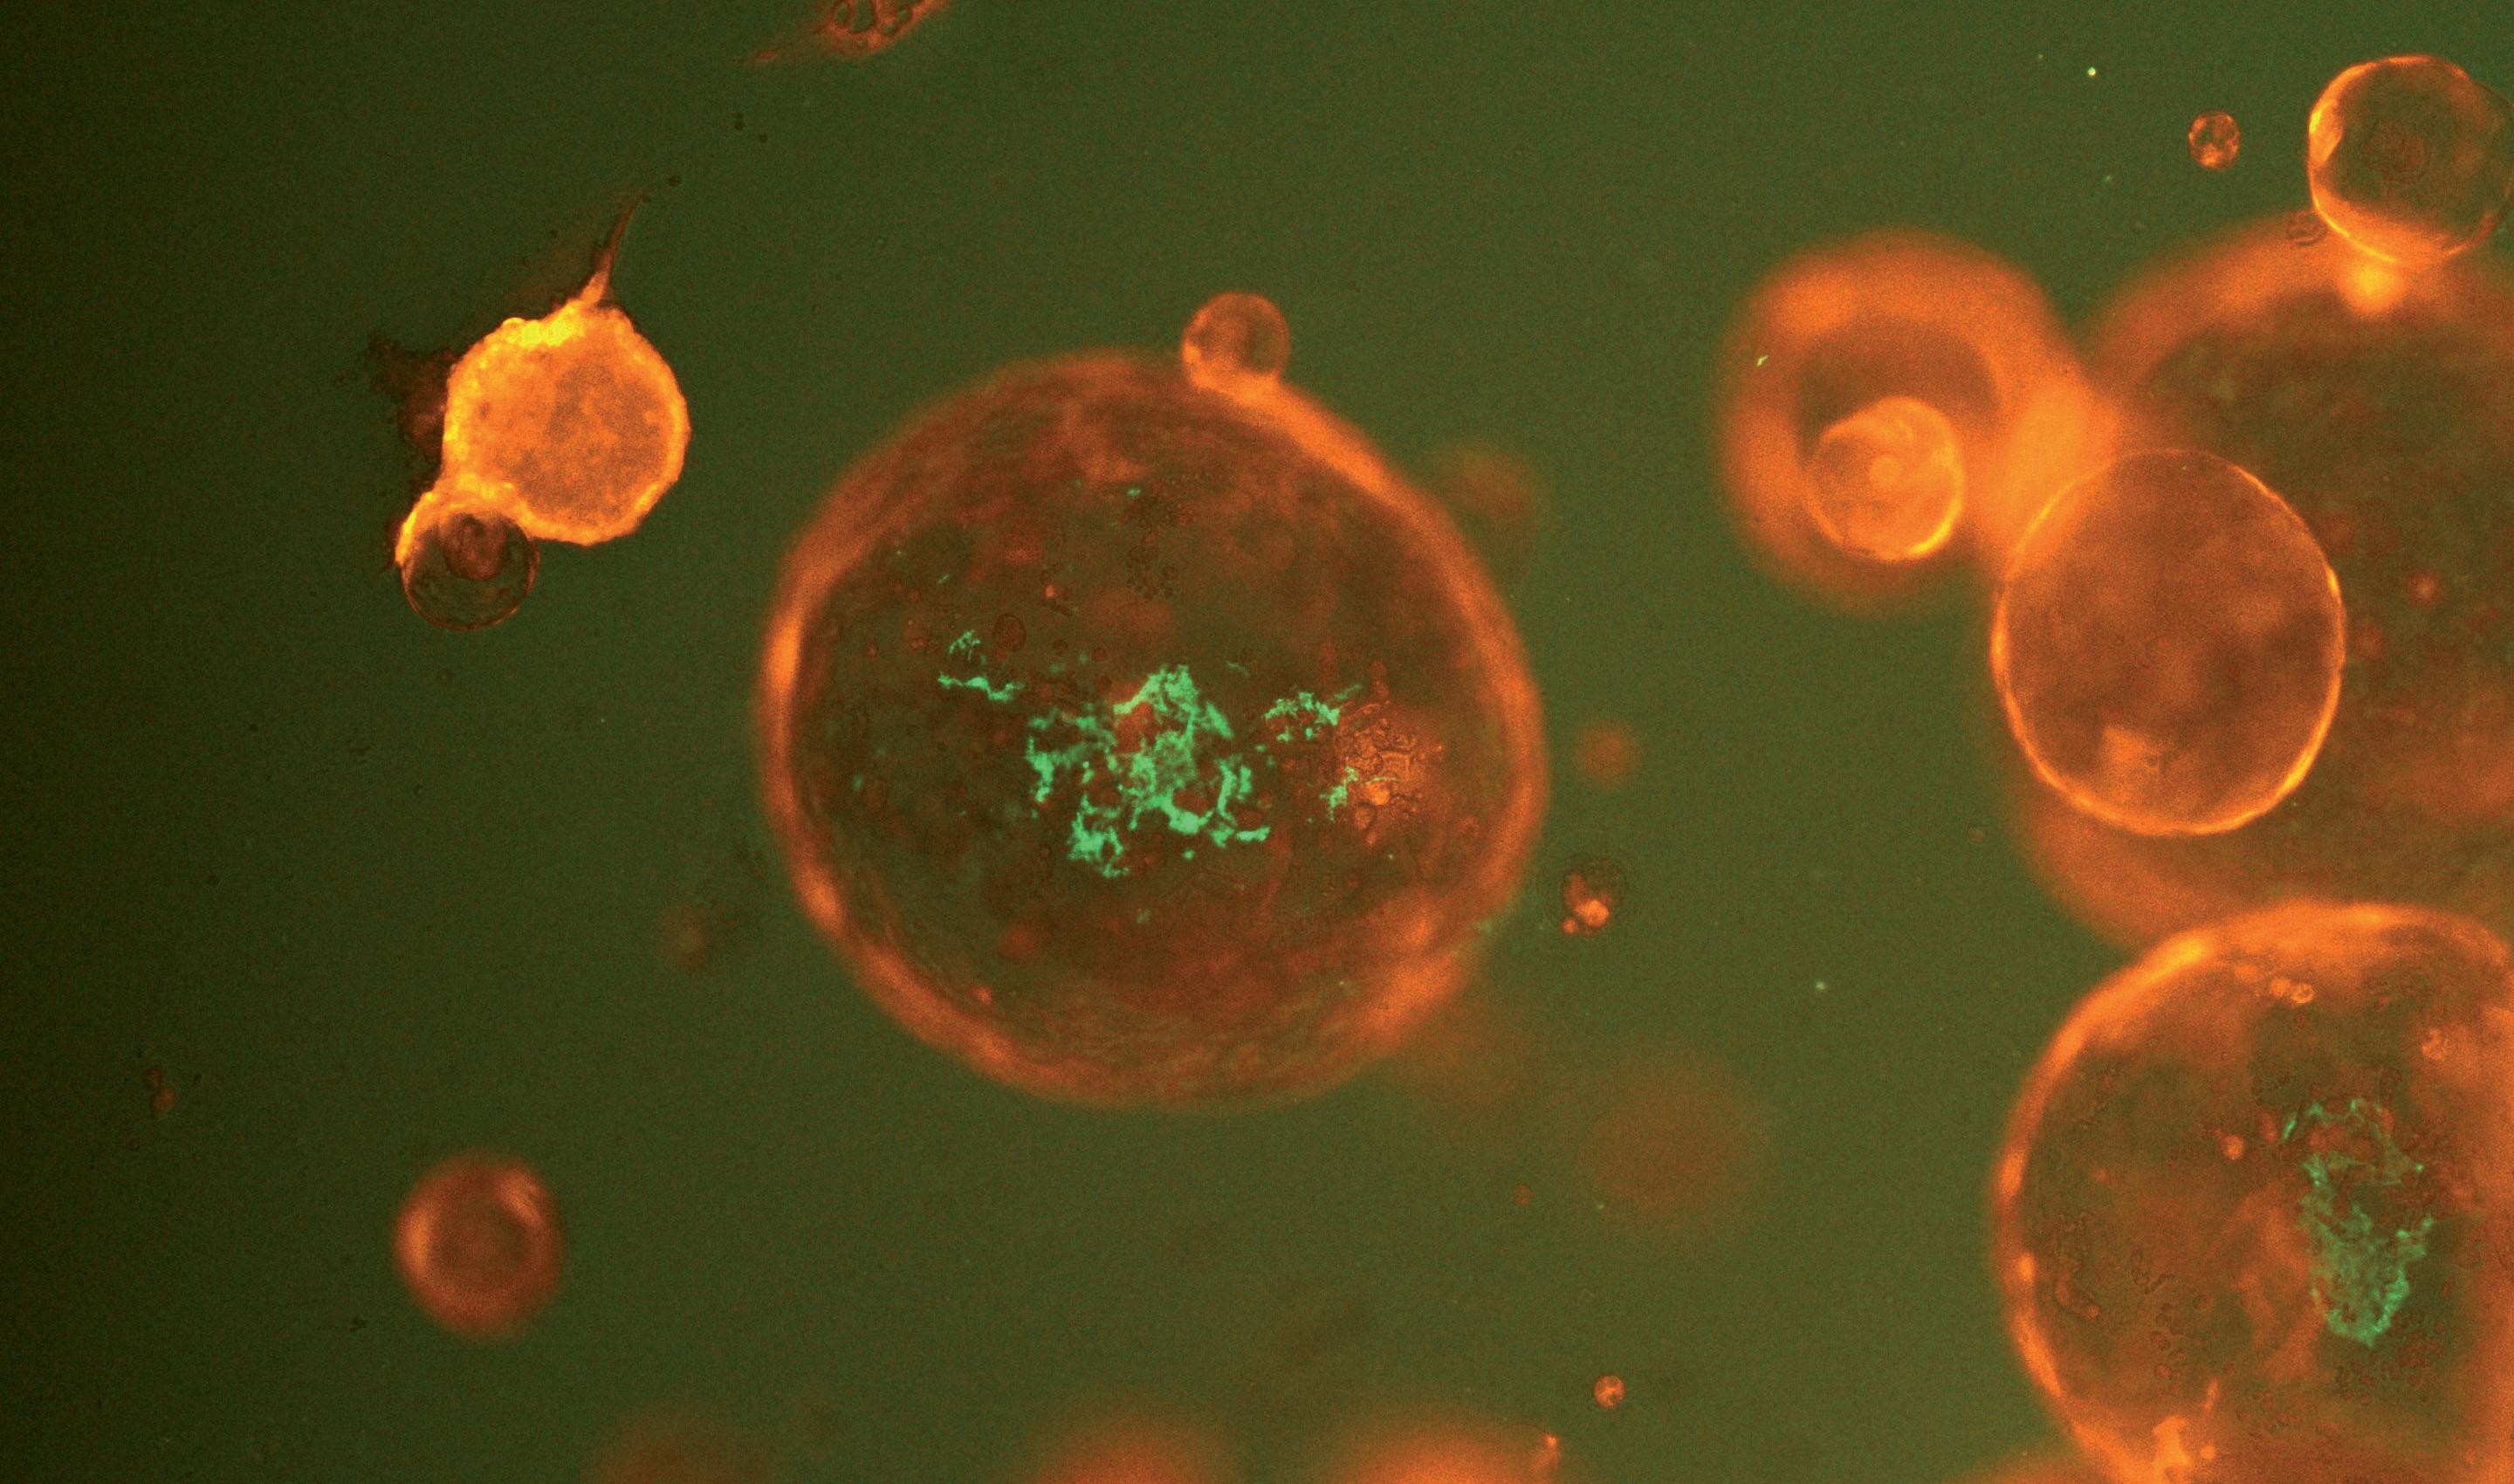

DerTraum von der Verlängerung unseres Lebens ist uralt, doch nie war er so aktuell wie heute. Und nie waren die Aussichten besser: Jung, aktiv, gesund und attraktiv zu bleiben, bis ins hohe Alter. Wissenschaftler haben in den vergangenen Jahren das große Rätsel unserer Vergänglichkeit entschlüsselt. Und sie haben erste Techniken entwickelt, die den Alterungsprozess kontrollieren. Der Wissenschaftsjournalist Ulrich Bahnsen schildert in seinem Buch „Das Uhrwerk des Lebens“ eine spannende Reise zu den weltweit führenden Alternsforschern. Sie entwickeln epigenetische Therapien, die unseren Körper um Jahrzehnte verjüngen können. Das Uhrwerk des Lebens kann wieder auf Jugend gestellt werden. Es ist eine Zäsur: Die Menschheit probt den Aufstand gegen den Tod.

komplizierte Rechenvorschrift für Computer, ein Algorithmus. Doch es sollte in den folgenden Jahren die gesamte Alterswissenschaft vom Kopf auf die Füsse stellen. Und Steve Horvath selbst, zuvor ein relativ unbekannter Genetiker und Bioinformatiker, erlebte den Aufstieg zu einem Superstar in der Welt der Wissenschaft, zu einem ernsthaften Kandidaten für einen künftigen Nobelpreis.

Ein Mann starrt auf Uhren

Steve Horvath war 2012 in seinem 45. Lebensjahr, als er an einem Tag in seinem Labor Zellen aus zwei Speichelproben untersuchte. Eine stammte von seinem Bruder Markus, die andere von ihm selbst. Und er entdeckte, was niemand für möglich gehalten hätte: Sein eineiiger Zwillingsbruder war tatsächlich 45, Steve aber bereits 50. Ausgeschlossen, oder?

Doch Horvath wusste zu diesem Zeitpunkt bereits, was das Ergebnis zu bedeuten hatte. „Es war der Moment, in dem ich zum health nut wurde, zu einem Gesundheitsapostel“, erzählte er mir im Juni 2019 in einem Gespräch während einer Konferenz in Rotterdam. Horvath begann mit Sport, stellte seine Ernährung um und verzichtete auf Nikotin. „Das war nicht einfach, ich habe so gern Zigaretten geraucht. Ich träume immer noch davon.“

Horvath war damals schon seit 12 Jahren Professor an der University of California Los Angeles (UCLA). Und das scheinbar widersinnige Ergebnis zeigte sein gerade erst fertig gebautes, ganz besonderes Chronometer an. Es misst eine sehr kostbare Sorte von Zeit: unsere Lebensspanne. Horvath ist kein Uhrmacher, sein Produkt konnte man nicht sehen oder anfassen und auch nirgendwo kaufen. Es war eine

Doch bis dahin würde es ein langer Weg sein. Steve heißt eigentlich Stephan, er ist in Frankfurt am Main aufgewachsen –und eigentlich beginnt dort auch die Geschichte seiner Uhr. Als Heranwachsende gründeten er, sein Buder und ihr gemeinsamer Freund Jörg Zimmermann den Debattenzirkel „Gilgamesch-Projekt“, eine Hommage an das berühmte sumerische Epos, das vor rund 4000 Jahren die Abenteuer des Königs Gilgamesch und seine vergebliche Suche nach der Unsterblichkeit schildert. Die jungen Leute diskutierten die großen Fragen der Menschheit, utopische Vorhaben aller Art. Vor allem aber: Sie wollten zu fernen Sonnensystemen fliegen. „Aber dann haben wir gemerkt – so ein Flug würde Hunderte Jahre dauern“, erzählt mir Horvath noch 2022, „wir mussten also erst das Altern stoppen lernen, bevor wir an Sternenreisen denken konnten“. Beim letzten Treffen versprach man sich, das ganze Leben diesem Ziel zu widmen. „Es war unser Gelübde“, sagt mir Jörg Zimmermann, als ich ihn 2023 auf die damaligen Ereignisse anspreche.

Wirklich Wort gehalten hat zunächst nur Steve Horvath. Sein Bruder wurde Psychiater und arbeitet heute in Long Beach, Kalifornien. Zimmermann forschte an Künstlicher Intelligenz, erst an der Universität Bonn, nun an der Hochschule Koblenz. Steve aber studierte Mathematik und Physik, machte seinen Doktor in den Vereinigten Staaten und lernte Biologie und Genetik, während er zusätzlich noch Bioinformatik an der Harvard University studierte.

Das Uhrwerk des Lebens Wie die Medizin den Code des Alterns entschlüssel

Autor: Dr. Ulrich Bahnsen

Herausgeber: Quadriga; 1. Aufl. 2023 Edition

ISBN-10: 3869951362

ISBN-13: 978-3869951362

Ulrich Bahnsen hat Biologie mit Schwerpunkt Biochemie und Zoologie studiert und 1992 mit einer molekulargenetischen Arbeit am Hamburger Uniklinikum promoviert. Er begann 1994 als Wissenschaftsjournalist zu arbeiten, war fester freier Autor beim „Spiegel“ und Redakteur beim Schweizer Nachrichtenmagazin „Facts“. Seit 2001 ist er Redakteur im Ressort Wissen der Zeit.

Für seine Artikel wurde er vielfach ausgezeichnet, unter anderem mit dem Best Cancer Reporter Award, dem Deutschen Medienpreis Neurologie und dem Medienpreis für Qualitätsjournalismus.

Seine Bücher: „Das Leben lesen. Was das Blut über unsere Zukunft verrät“, 2017 bei Droemer. „Das Ende aller Leiden“ 2022 bei Lübbe Quadriga. „Das Uhrwerk des Lebens“ 2023 bei Lübbe Quadriga.